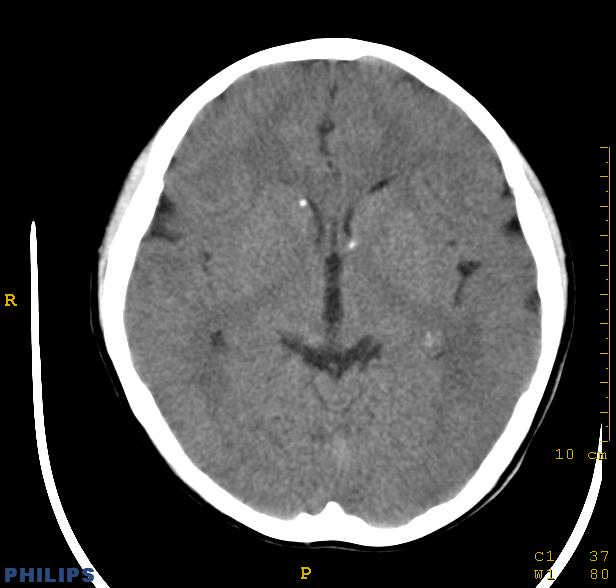

标题: PED0043:头颅平扫 男12岁.典型结节性硬化 [打印本页]

标题: PED0043:头颅平扫 男12岁.典型结节性硬化

典型结节性硬化

[影像学表现]

1.ct表现:

①室管膜下有多发性小结节状钙化影,也可为单发、不强化;小结节亦可未钙化;突入脑室可以强化;但有钙化者居多,颅内异常钙化高达90%。一般出生后2年即呈典型钙化。

②10%-15%的病例可能恶变为室管膜下巨细胞星形细胞瘤或其他胶质瘤。前者常位于室间孔附近,生长缓慢,增强扫描可产生异常强化。